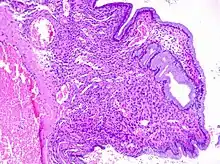

Cervical polyps can be seen during a pelvic examination as cherry-red or greyish-white projections from the cervical canal.[2] Diagnosis can be confirmed by a cervical biopsy which will reveal the nature of the cells present.[3]

Structure

Cervical polyps are finger-like growths, generally less than 1 cm in diameter.[1] They are generally bright red in colour, with a spongy texture.[6] They may be attached to the cervix by a stalk (pedunculated) and occasionally prolapse into the vagina where they can be mistaken for endometrial polyps or submucosal fibroids.[4]